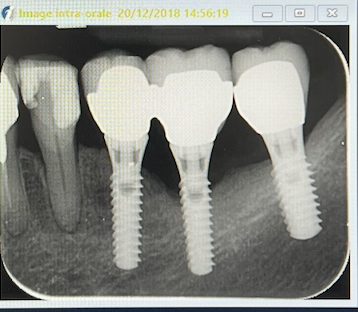

radio le 2O/12/2018